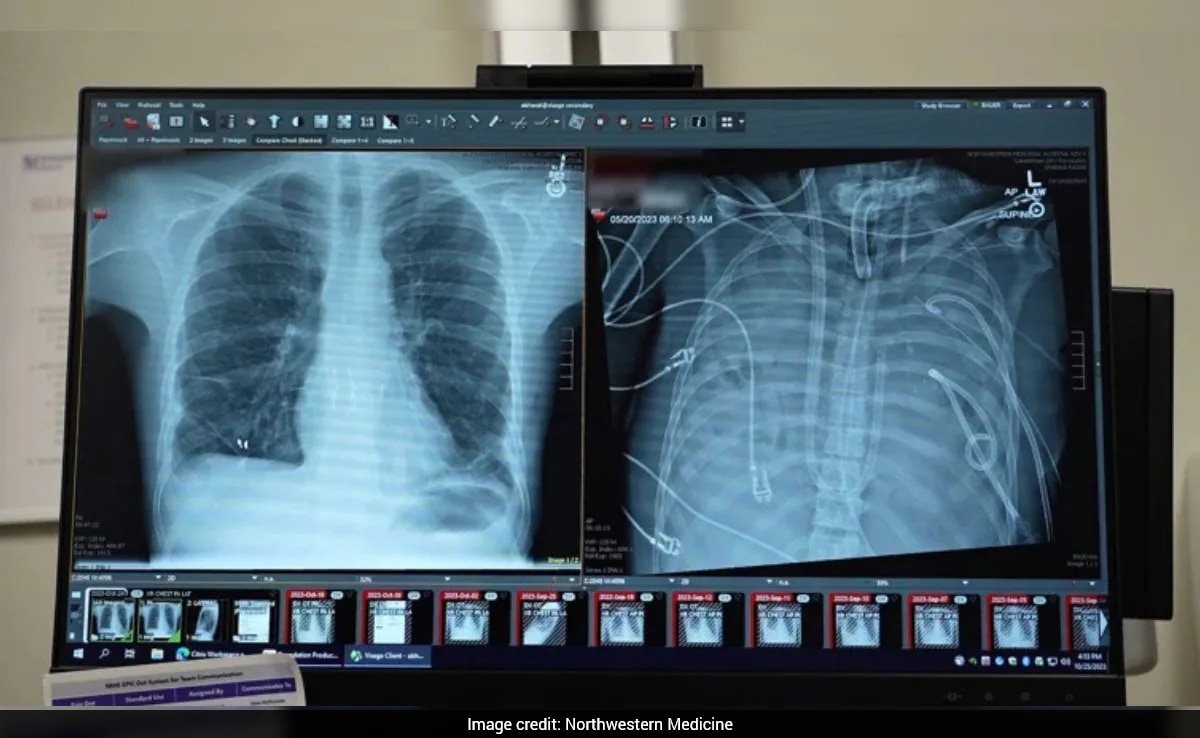

A 33-year-old patient was able to survive for 48 hours without lungs because of a groundbreaking medical procedure. In an article published by Nature, it was revealed that the patient, who was suffering from a severe lung infection, underwent a pioneering operation where his damaged lungs were removed and an artificial lung system was used to oxygenate his blood.

The procedure, led by Dr Ankit Bharat, thoracic surgeon at Northwestern University Feinberg School of Medicine in Chicago, Illinois, involved removing the patient's lungs and using a machine to oxygenate his blood.

"Once the infected lungs were removed, the patient's condition improved. His blood pressure stabilized, organ function recovered, and the infection subsided. Two days later, donor lungs became available, and the surgeons performed a double lung transplant. More than two years later, the patient has returned to daily life with good lung function," the press relese noted.